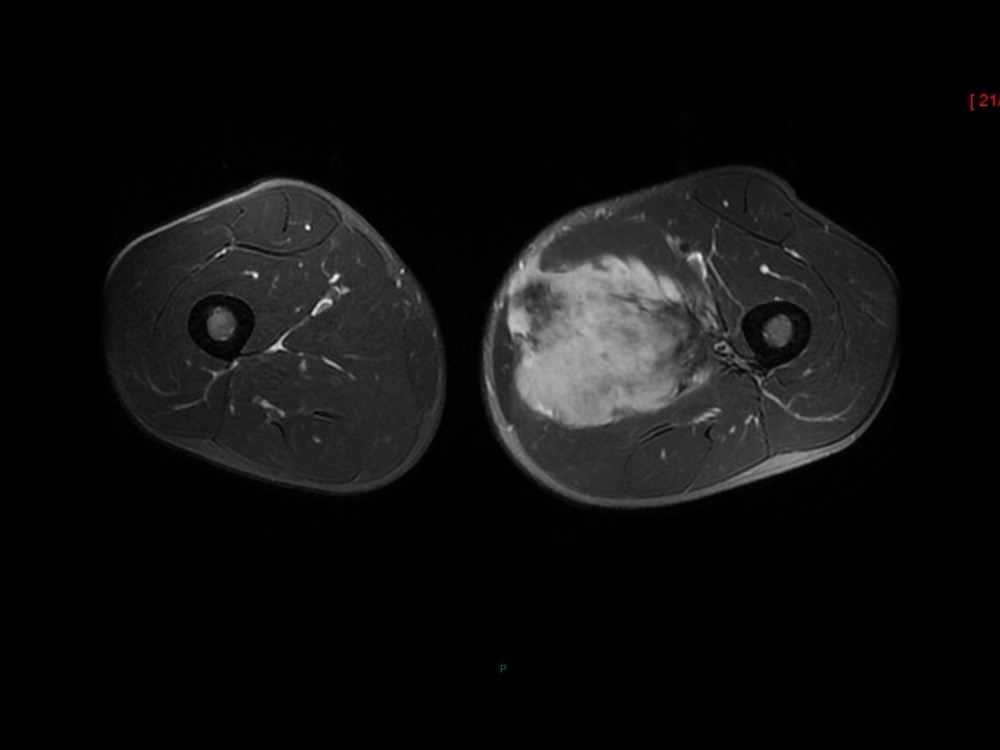

Moalla / Mihoubi-Bouvier / Drapé 18/05/2022